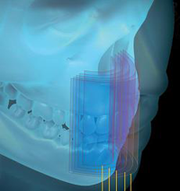

Skany cienkowarstwowe (funkcja 2D+) oferują większą możliwość

niż standardowy obraz dwuwymiarowy.

Dzięki wysokiej ostrości skanom wycinkowym lekarz szybciej

i precyzyjniej może ustalić położenie zębów nadliczbowych

i zatrzymanych, oceni zmiany wierzchołkowe, a także określi relację korzenia z wyrostkiem zębowym.